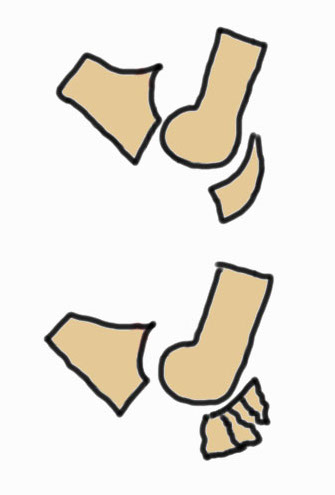

Mayo Classification

A: Non comminuted

B: Comminuted

| Type I | Type II | Type III |

|---|---|---|

| Minimally displaced | Displaced | Trans-olecranon fracture dislocation |

| 10% | 85% | 5% |